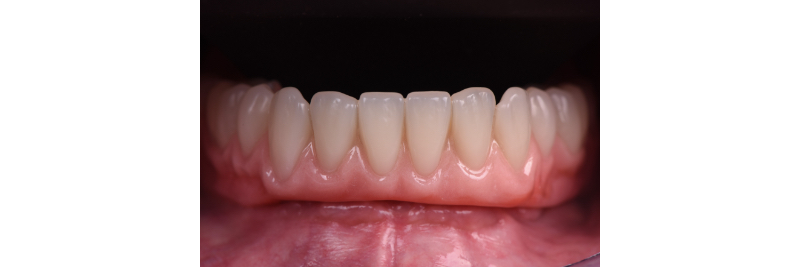

Front view of the implant hybrid prosthesis intraorally.